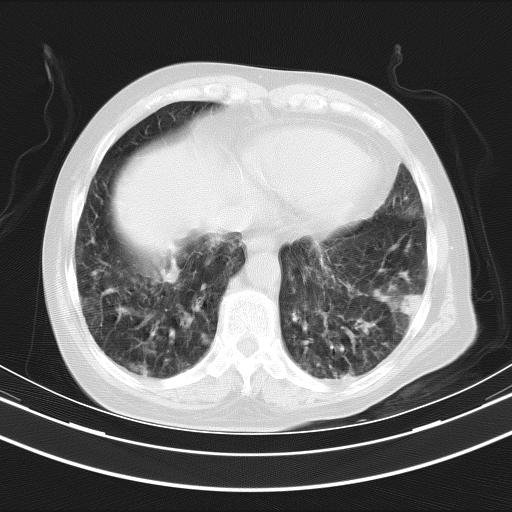

老年女性,嗜睡3天,意识模糊。轻咳,无发热。

两肺慢支炎伴感染,左侧胸腔积液。纵膈及双侧肺门淋巴结肿大建议复查。

双肺多发淡片影,毛玻璃影,,支持支气管肺炎,,建议血气找原因,,嗜睡是否肺性脑病?有没有慢支病史?

双肺炎症,建议抗炎治疗后复查,见过几个老年肺炎病例,没有发烧、咳嗽症状,直接以昏迷就诊。

1)两肺感染性病变;建议抗炎治疗后复查。2)纵隔淋巴结肿大。3)左侧胸腔积液。